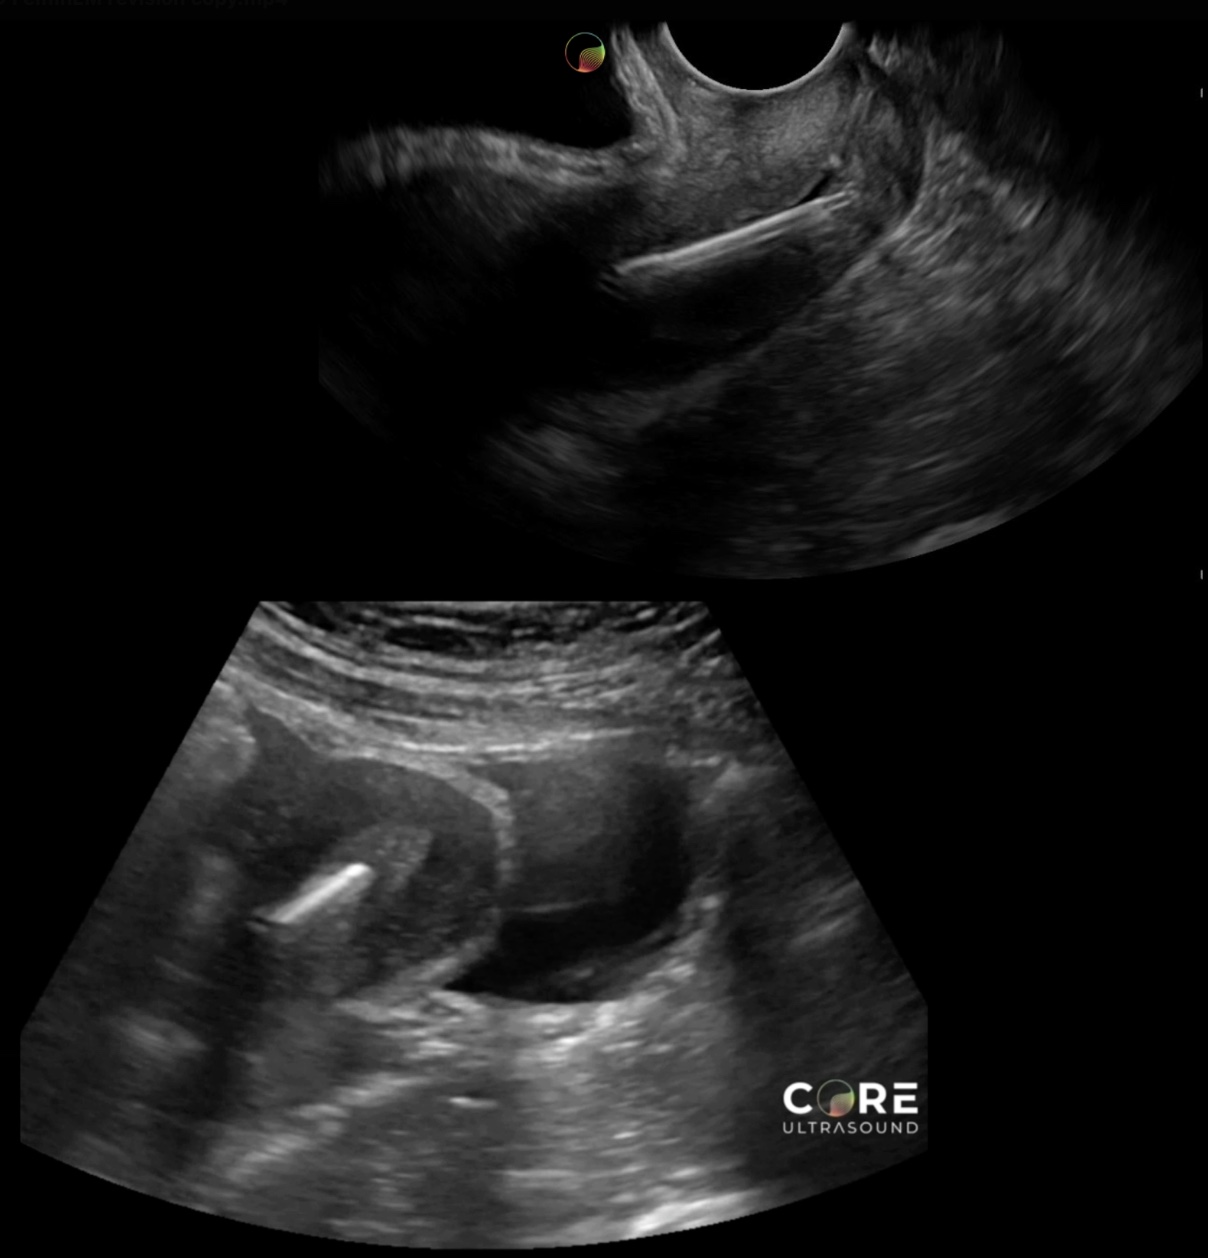

Check out our other POCUS lectures: - POCUS Basics: GYN Scanning Techniques - POCUS Basics: Intrauterine Pregnancy and Early Pregnancy Loss - POCUS Basics: Ectopic Pregnancy